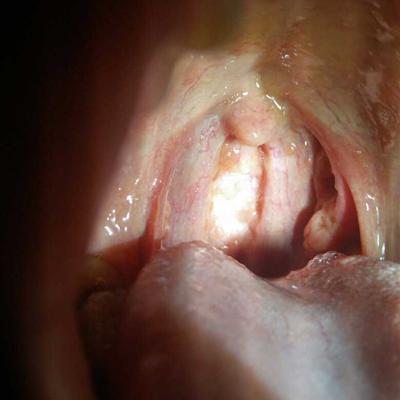

Patients with bronchitis attack when breathing is not smooth, because the inflammation of the trachea inside the sputum is more. So in the treatment of bronchitis, many people want to start from the treatment of phlegm, so that they can reduce the symptoms of bronchitis attack. Now share with you, in daily life, bronchitis patients should be how to phlegm!

How does bronchitis resolve phlegm?